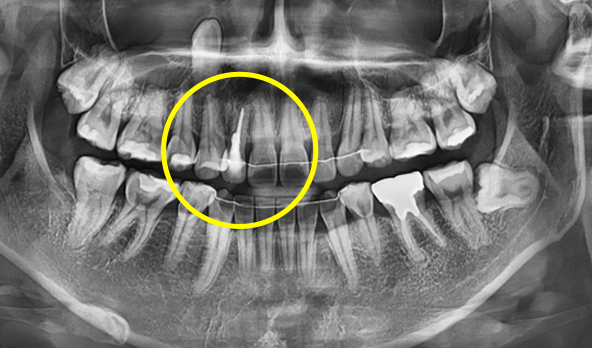

3D 모의 수술로 최적 식립 위치 계산

3차원 CT사진과 구강스캐너를 이용하여

미리 가상의 수술을 거쳐서 수술 위치를 정하고

수술 후 상부 위치까지 예측해서